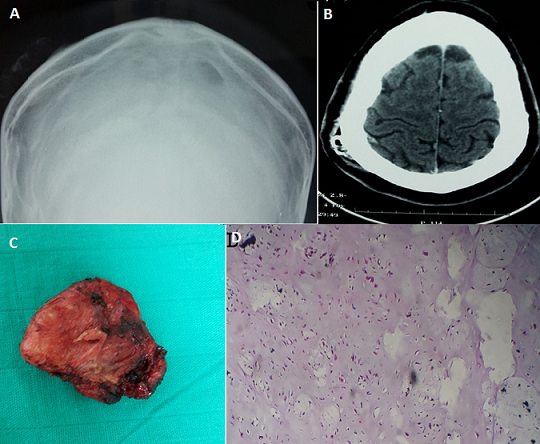

A 26 year old man, with no specific past or family history, presented with slow growing subcutaneous mass in the right parietal region of about 4 cm. Skin examination revealed a firm subcutaneous nodule that was movable over the underlying bone. Physical examination was not remarkable other than above-described skin lesion. X-rays of the skull (A) and CT scan (B) showed a subcutaneous mass next to the right parietal eminence measuring 17×39 mm and containing calcifications. Surgery resection of the tumor was complete and easy (C). The nodule was not attached to underlying skull. The postoperative course was unremarkable. Histological examination confirmed the diagnosis of soft-tissue chondroma (D). Extraskeletal chondroma is a rare, benign cartilaginous tumor of the soft tissue. It presents as a solitary subcutaneous mass measuring less than 3 cm in diameter that is usually painless and slowly growing. It is most frequently found in the hands and feet of adults in the fourth and fifth decades. Its location in the scalp is exceptional and atypical. Complete excision is recommended for the treatment of extra skeletal chondroma.